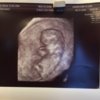

Er 13+4 i dagHar vært til privat ultralyd i dag, en herlig opplevelse! Alt så normalt ut, og lengden tilsvarte samme termin jeg allerede har fåttDet gikk ikke an å se kjønn, men det var en aktiv liten krabat som snudde seg rundt og veivet med både armer og bein!

![]()

Vis vedlegget 92825Vis vedlegget 92827